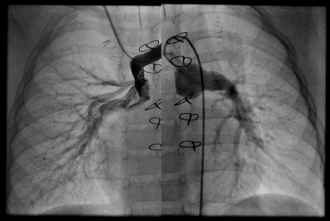

MAPCA症例 4本のMAPCAが有する症例

肺動脈統合術(unifocalizaton)術後 矢印の部分が狭窄病変